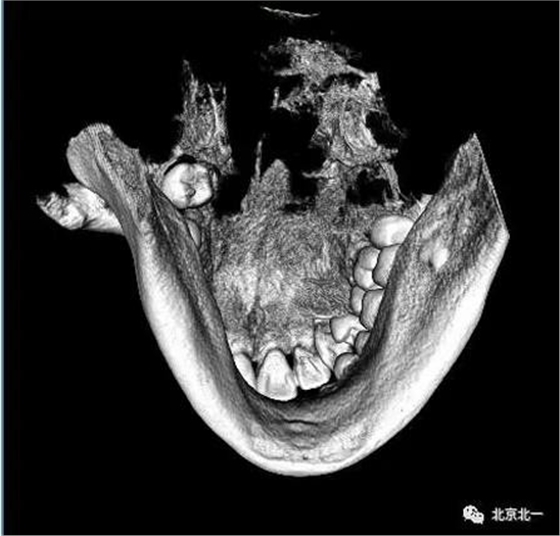

圖四:三維重建

圖五:三維重建可見牙冠突破舌側